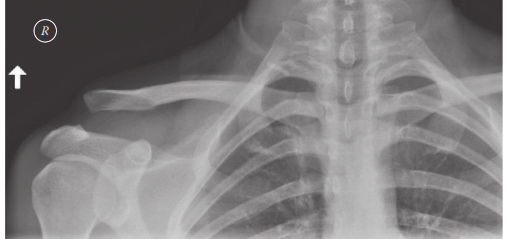

الأشعة السينية العادية (Plain Radiographs):

- المنظر الأمامي الخلفي (AP View): لتقييم محاذاة الترقوة والأخرم.

- منظر زانكا (Zanca View): يُعد هذا المنظر أساسيًا، حيث يتم تصوير الكتف بإمالة 10-15 درجة لأعلى، مما يتيح رؤية واضحة لمفصل الترقوة الأخرمي دون تداخل من لوح الكتف.

- المنظر الجانبي الإبطي (Axillary Lateral View): لتقييم أي إزاحة خلفية أو أمامية للترقوة.

- صور الأشعة مع الأوزان (Stress Views): يتم أخذها أحيانًا مع حمل المريض لأوزان (10-15 رطلاً) في كل يد. يمكن أن تساعد هذه الصور في تشخيص الإصابات الخفية من النوع الثاني أو الثالث عن طريق إبراز الإزاحة العمودية، على الرغم من أن فائدتها محل نقاش بسبب الانزعاج المحتمل ونتائجها غير المؤكدة.

- قياس المسافة الغرابية الترقوية (Coracoclavicular Distance): يُعد هذا القياس على الأشعة السينية الأمامية الخلفية حاسمًا، حيث أن زيادته تشير إلى تمزق في الأربطة الغرابية الترقوية.